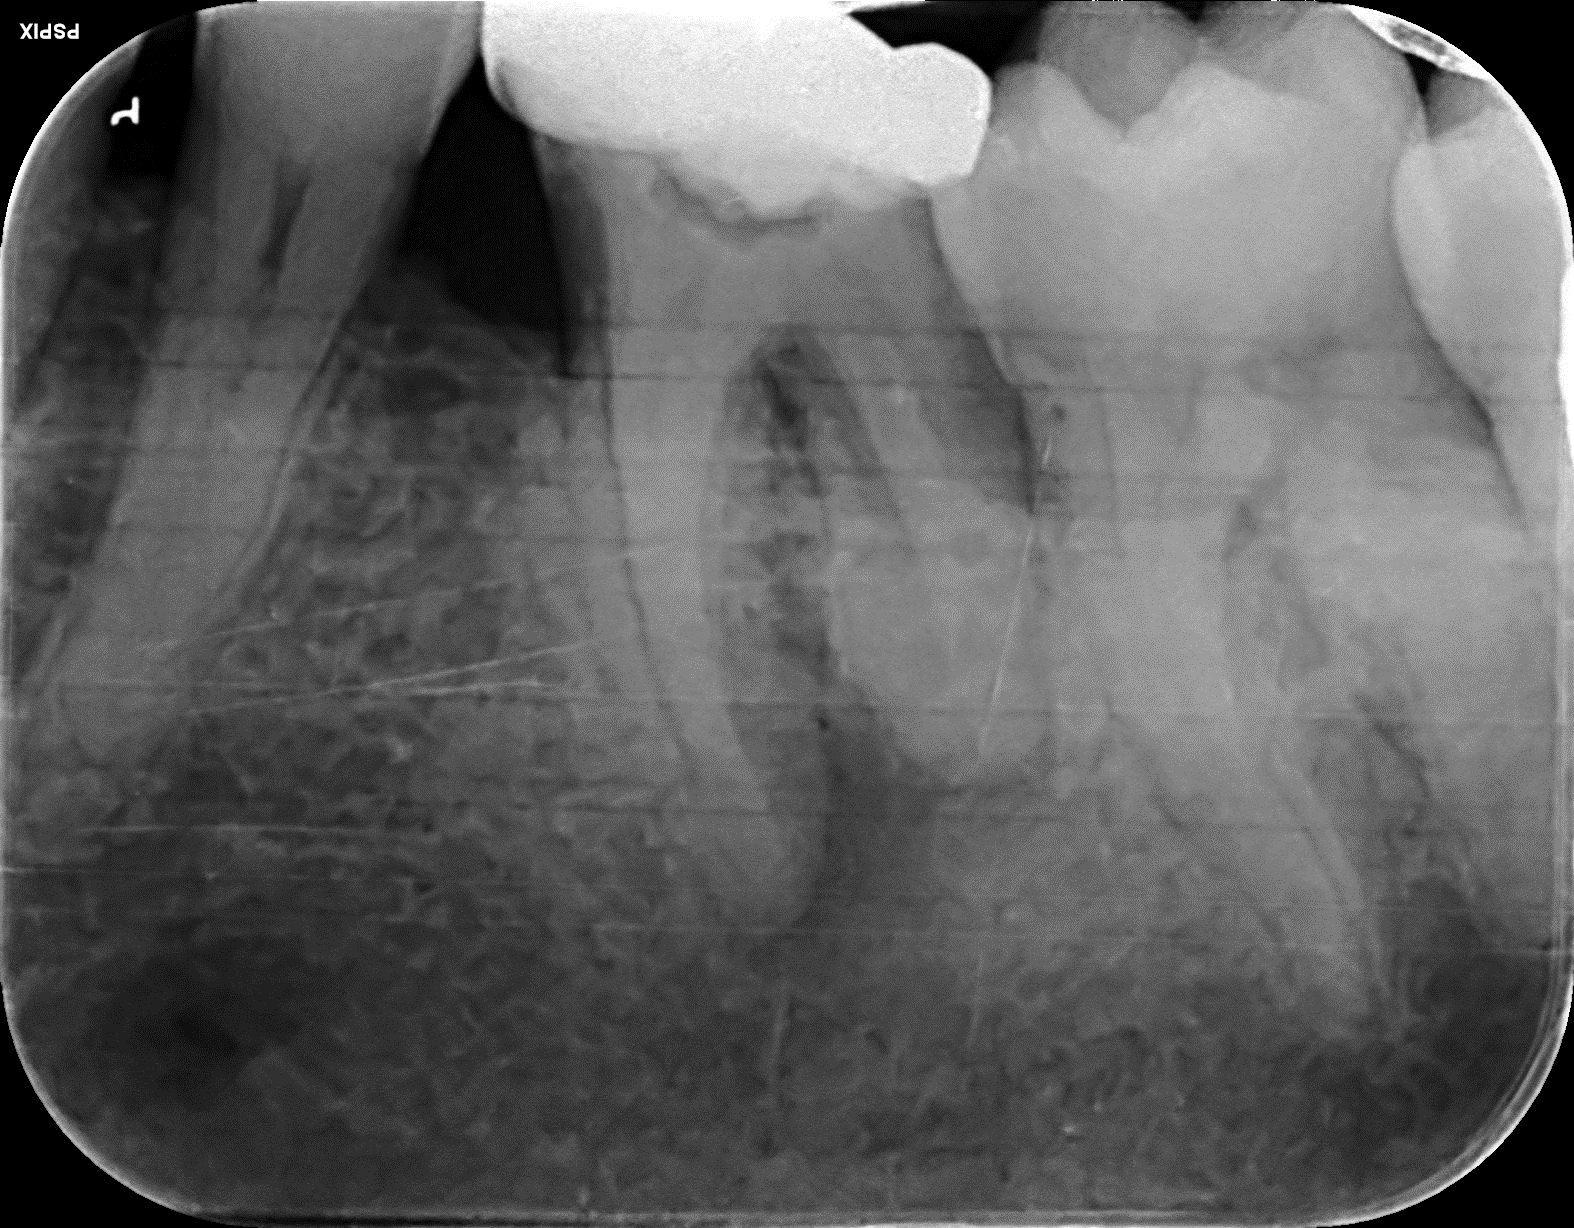

Lower Molar curved roots Re-root canal treatment with core rebuild